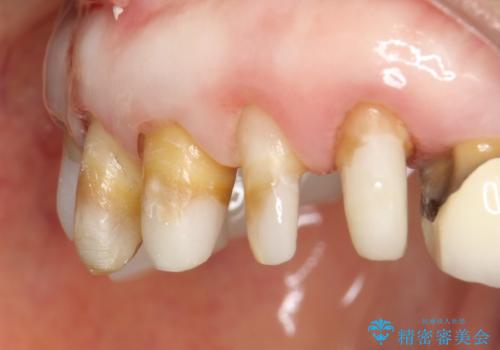

前歯の低クオリティな治療の実態 妥協無い治療で根本からやり治す

・虫歯がとりきれていない

・接触部分がガタガタで適合の悪い金属

・全く無菌の努力がされていない根管治療

など、いい加減な治療は「治療」ではなく、むしろ医原性に歯の寿命を短くします。

最もよくないのは、クオリティの低い治療を何度も繰り返すことです。